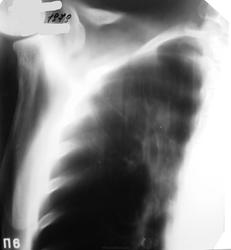

Справа дополнительная тень,с просветлением ,с неровными ,не четкими контурами связанная с корнем,больше данных за tbcфиброзно-каверзно зная форма.

Кольцевидная тень верхней доли правого легкого с неравномерной стенкой, наибольшей по толщине с "1 по 3 ч", полостью распада с неровным достаточно ясным контуром. Секвестров не отмечено. Внешний контур также ясный (термин, невилирующий разницу между "размытый" и "четкий"). Видны перифокальные очаги мелких и средних размеров ниже и медиальнее "кольца". Перибронхиальная инфильтрация прилежащих бронхов. В дифф.ряд поставил бы всё выше указанное с акцентом на инф.туб. с распадом.